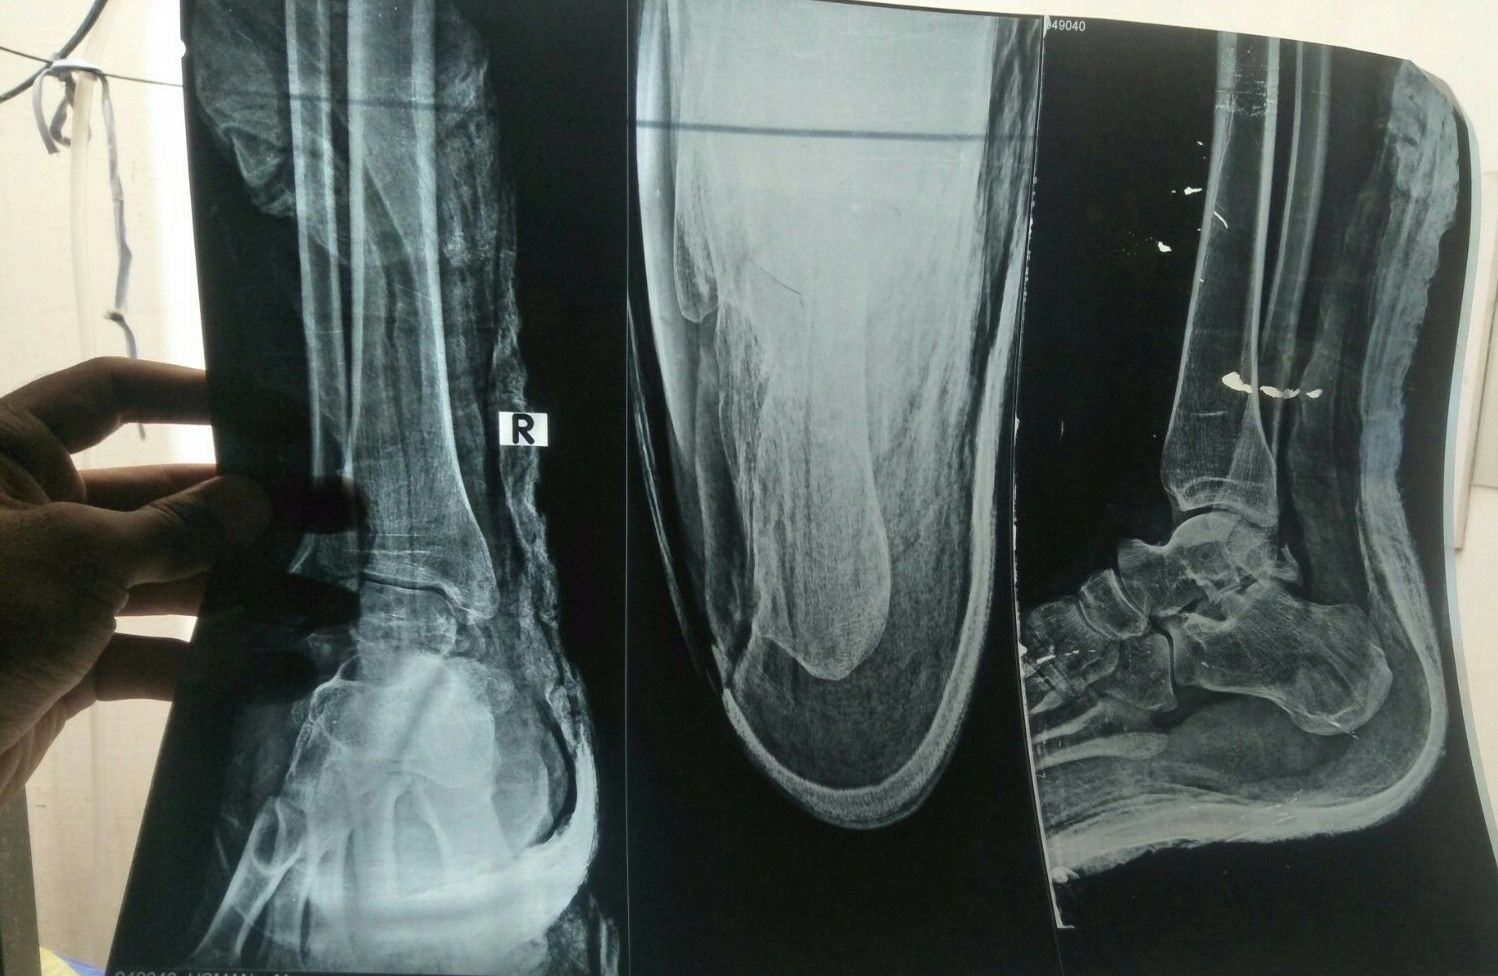

Aoa Dctr Sahb Sugest me.. Ye ankle m nut dala three month ho gye h ... Ub doctor bol rha niklwa lo ub.. Kia ye abi niklwana chye ?? Abi thk chl rha bs thora sa lungra ky chlta wazan b pura dlta h.... Kia ye 1 week m cover ho jaey ga?? niklwa lia wazan dal jaey ga or again pluster ho ga??

Ye h Xray phla jb fracture hoa tha... Dctr bol Rha h Abi nikal Dyty h...

Ye phly X'ray h jb fracture hoa tha... Dctr bol rha ub nikl dyty h... Trouble kch b ni easy h... Lungra ky Chlta h or swelling rahti jb chlta h....

Obviously the screw is large and protruding outside the bone from front causing pain and difficulty in walking.

Ye phla xray jb fractured hoa tha...

Ye phla xray h .. Jb fractured hoa tha....

Phla xray h ye ... Ap kia suggest krty or kb tuk recover ho ga ye ??

Ye x ary

Ye hai Sir ....

Xray Before operate yehi hoa h...